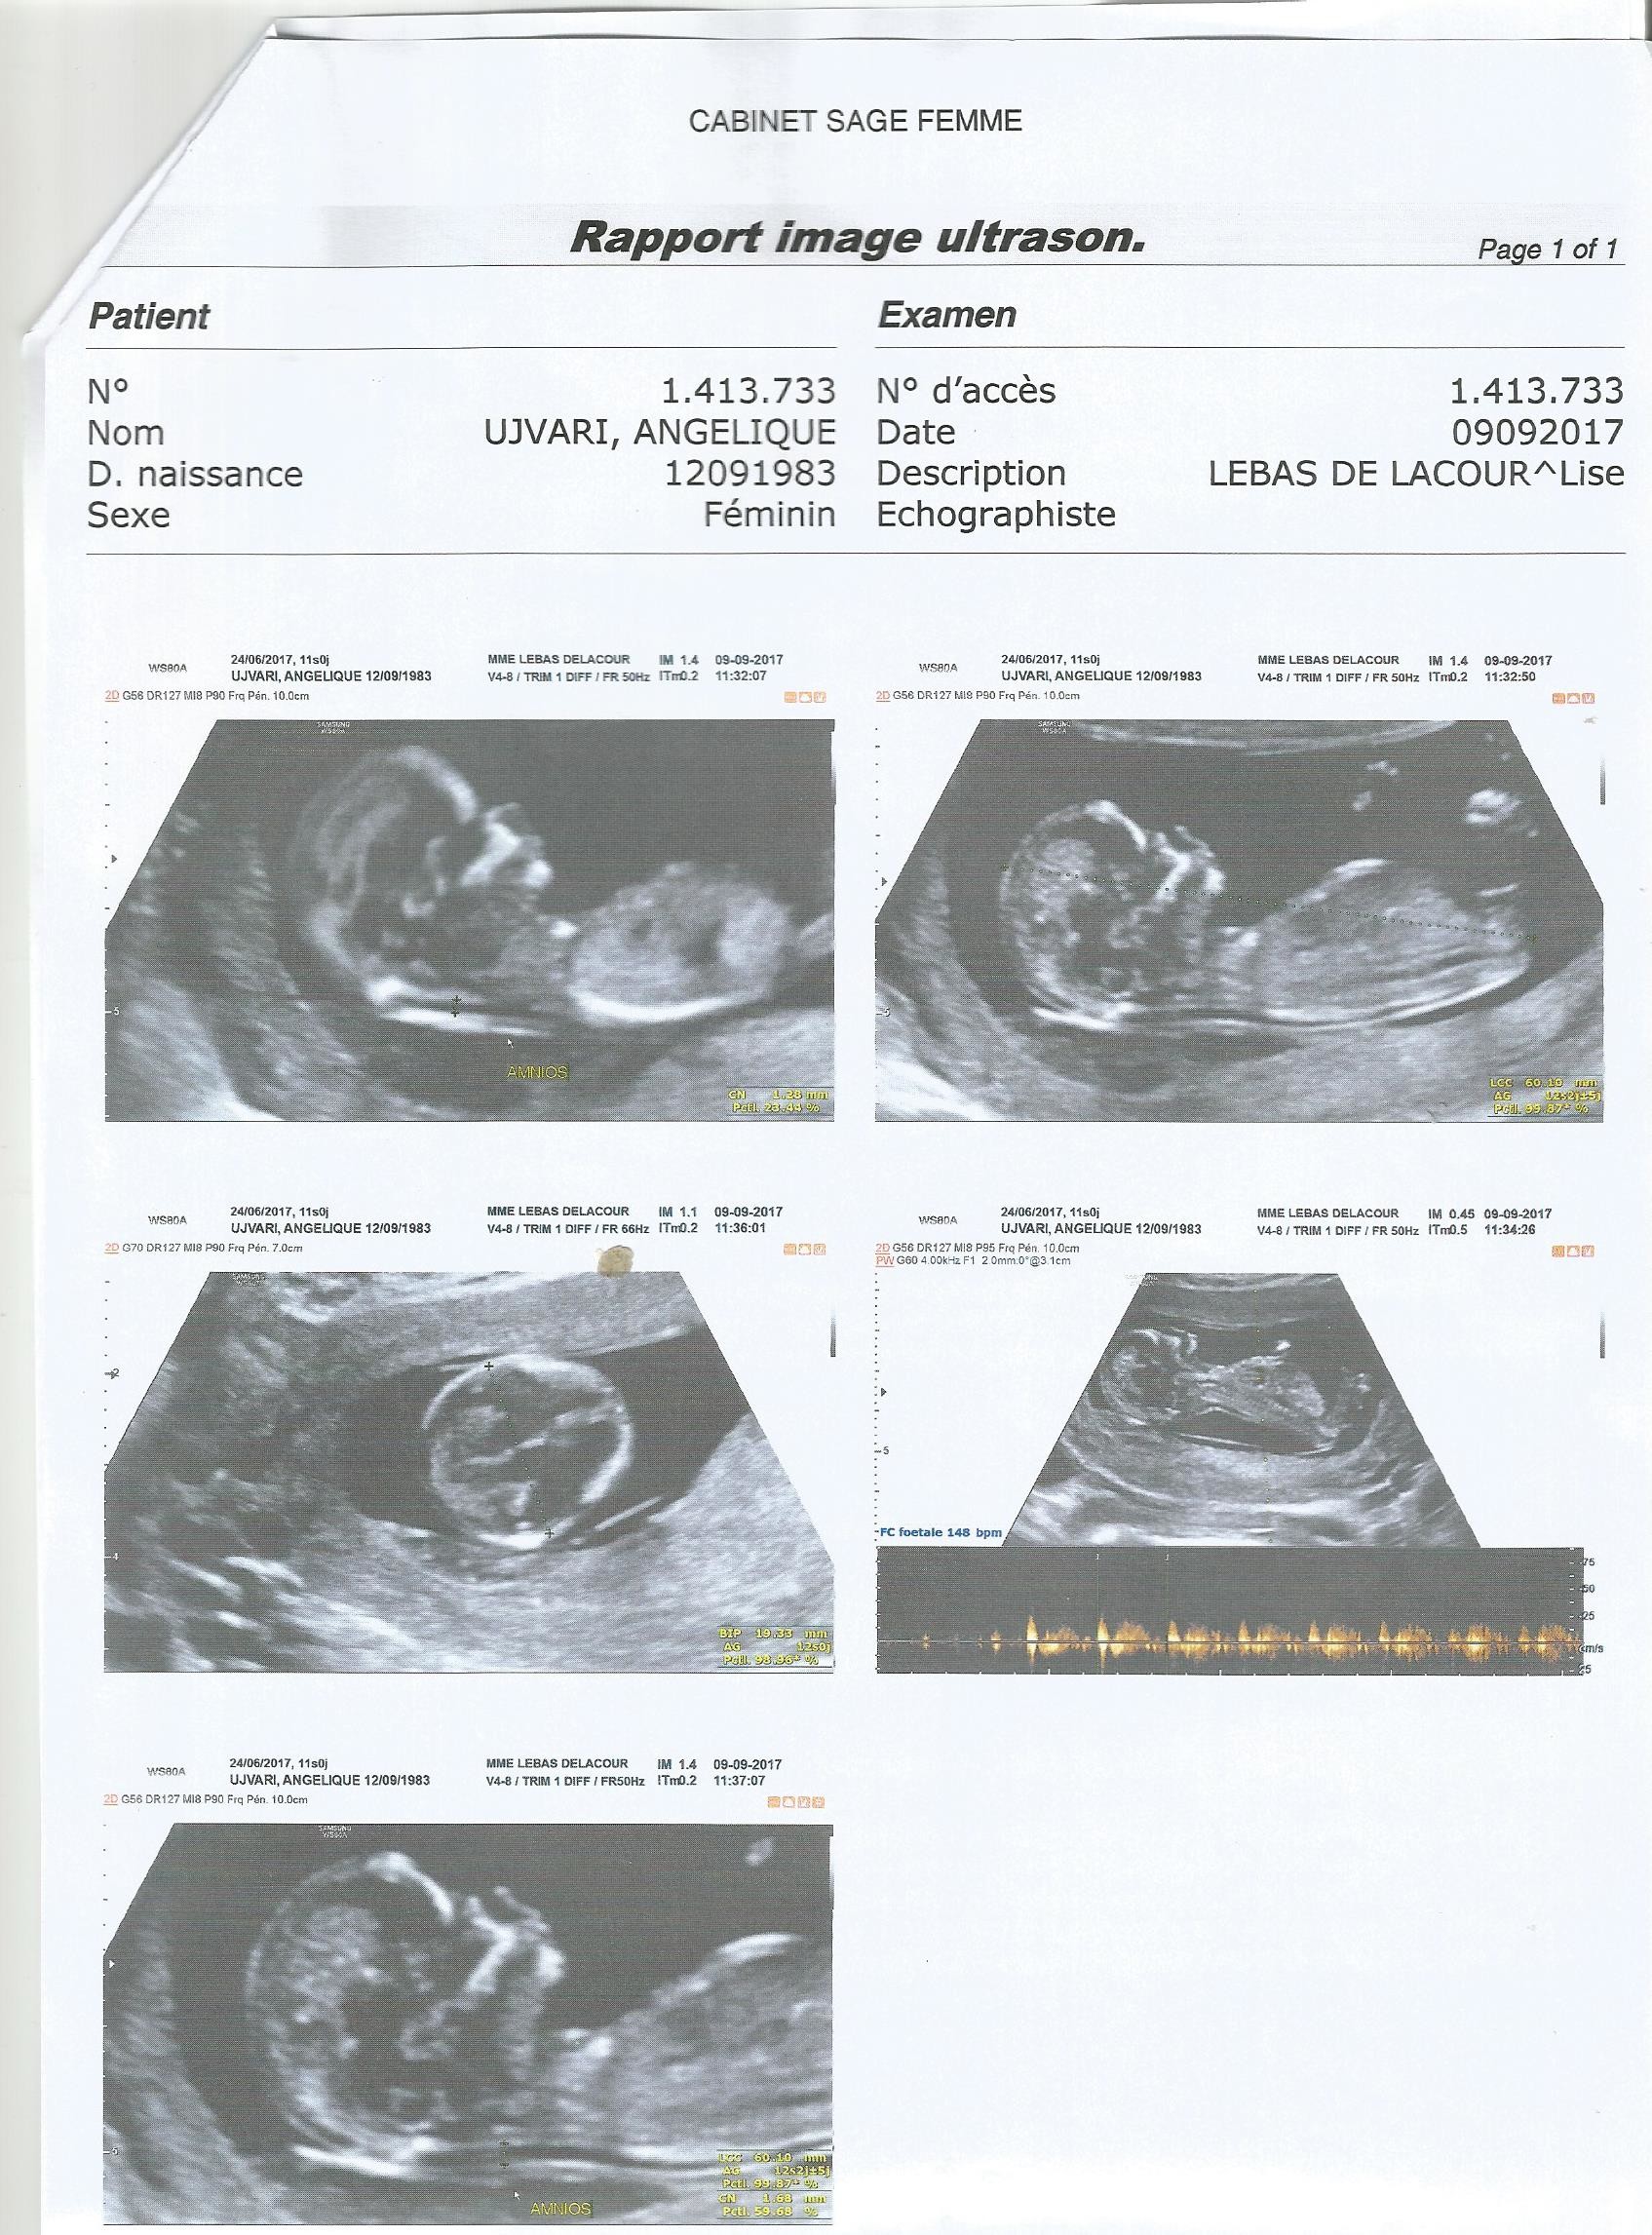

Battements du coeur. Selon vous filles ou garcon. Alors moi a 6 sa 3 son cœur battait a 127 bpm et a 8 sa 3 entre 160 et 180 bpm. Battement du cœur fille ou garcon.